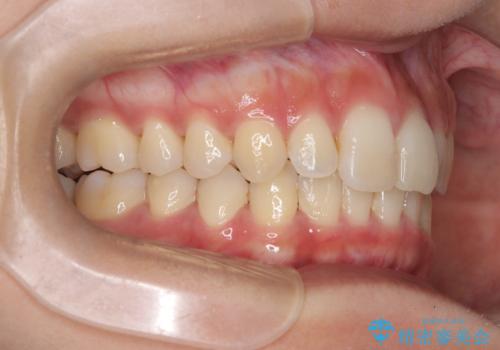

ディープバイト改善のためのインビザライン治療

- 患者様は、全体的な歯列のガタガタとディープバイト(深い噛み合わせ)を主訴として来院されました。診断の結果、ディープバイトを改善するためには、歯列全体の拡大が必要であると判断しました。治療には、透明なマウスピース型矯正装置「インビザライン」を使用し、歯を適切に拡大しながら歯並びを整える計画を立てました。治療期間はおおよそ2年を見込んで進め、最終的に見た目にも大きく変化をもたらすことを目指しました。

ディープバイトの治療には、奥歯の高さや前歯の位置に対する繊細な調整が必要です。本症例では、インビザラインによる歯列拡大を行うことで、噛み合わせを改善し、歯並び全体を整えました。治療過程では、歯間のスペースを確保するため、IPR(インタープロキシマルリダクション)を適宜行い、無理なく歯列の調整を行いました。治療後は、歯並びが大きく改善され、患者様の見た目にも大きな変化が現れました。インビザラインは透明で目立たず、治療中の見た目を気にされる患者様にも配慮した治療法です。